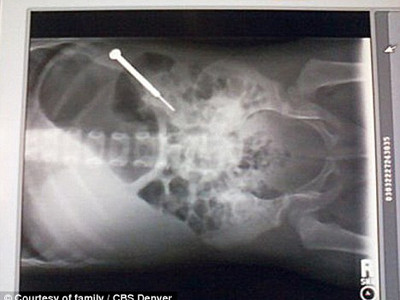

Ngay khi được đưa đến Trung tâm y tế ở San Luis thuộc Alamosa, các bác sĩ đã nhanh chóng cấp cứu cho bé. Hình ảnh phim chụp X-quang cho thấy cô bé nuốt phải chiếc tua vít xấp xỉ 9 cm.

| Hình ảnh chụp X-quang tua vít dài 3,5 inch ( xấp xỉ 9cm). |

Các bác sĩ phẫu thuật đã phải làm việc gần một giờ đồng hồ để lấy chiếc tua vít mà được dùng chủ yếu vào việc siết chặt kính ra khỏi ruột già của cô bé.